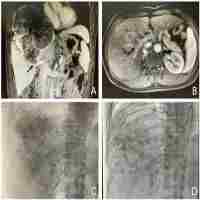

| Abstract | Background It is controversial whether patients with hepatocellular carcinoma (HCC) with portal vein tumor thrombus (PVTT) should undergo salvage surgery following the combination therapy of tyrosine kinase inhibitors (TKIs) and programmed cell death protein 1 (PD-1) inhibitors. This study aimed to elucidate the efficiency and safety of salvage surgery following combination therapy, while also summarizing a novel surgical approach for Vp3/4 PVTT. Methods Between April 2019 and December 2022, a consecutive series of unresectable HCC patients with PVTT who received salvage surgery following combination therapy were enrolled. Evaluation included perioperative and long-term follow-up outcomes. The complete removal of Vp3/4 PVTT was achieved using a novel surgical approach characterized by “longitudinal incision and transverse suturing” and “angle-to-straight conversion”. Results Forty patients including 22 patients with Vp3 and 18 patients with Vp4 were included. Long-term follow-up showed similar rates of portal vein patency (Vp3: 95.5%, Vp4:94.4%, p = 0.900), and 3-year portal vein patency rates were 95.0%. There were no significant differences observed in combination therapy-related adverse events (p = 0.253) and perioperative complications (p = 0.613) between the Vp3 and Vp4 groups. The recurrence patterns were similar between the two groups (p = 0.131). There were no significant differences in overall survival (OS) and recurrence-free (RFS) survival between the Vp3 and Vp4 groups (OS p = 0.457, RFS p = 0.985). Patients who achieved a pathological complete response had significantly better RFS (p = 0.011). Conclusion Salvage surgery after combination therapy demonstrated favorable efficacy and safety. The novel surgical approach for PVTT can effectively achieve complete removal of PVTT and ensured long-term portal vein patency. |